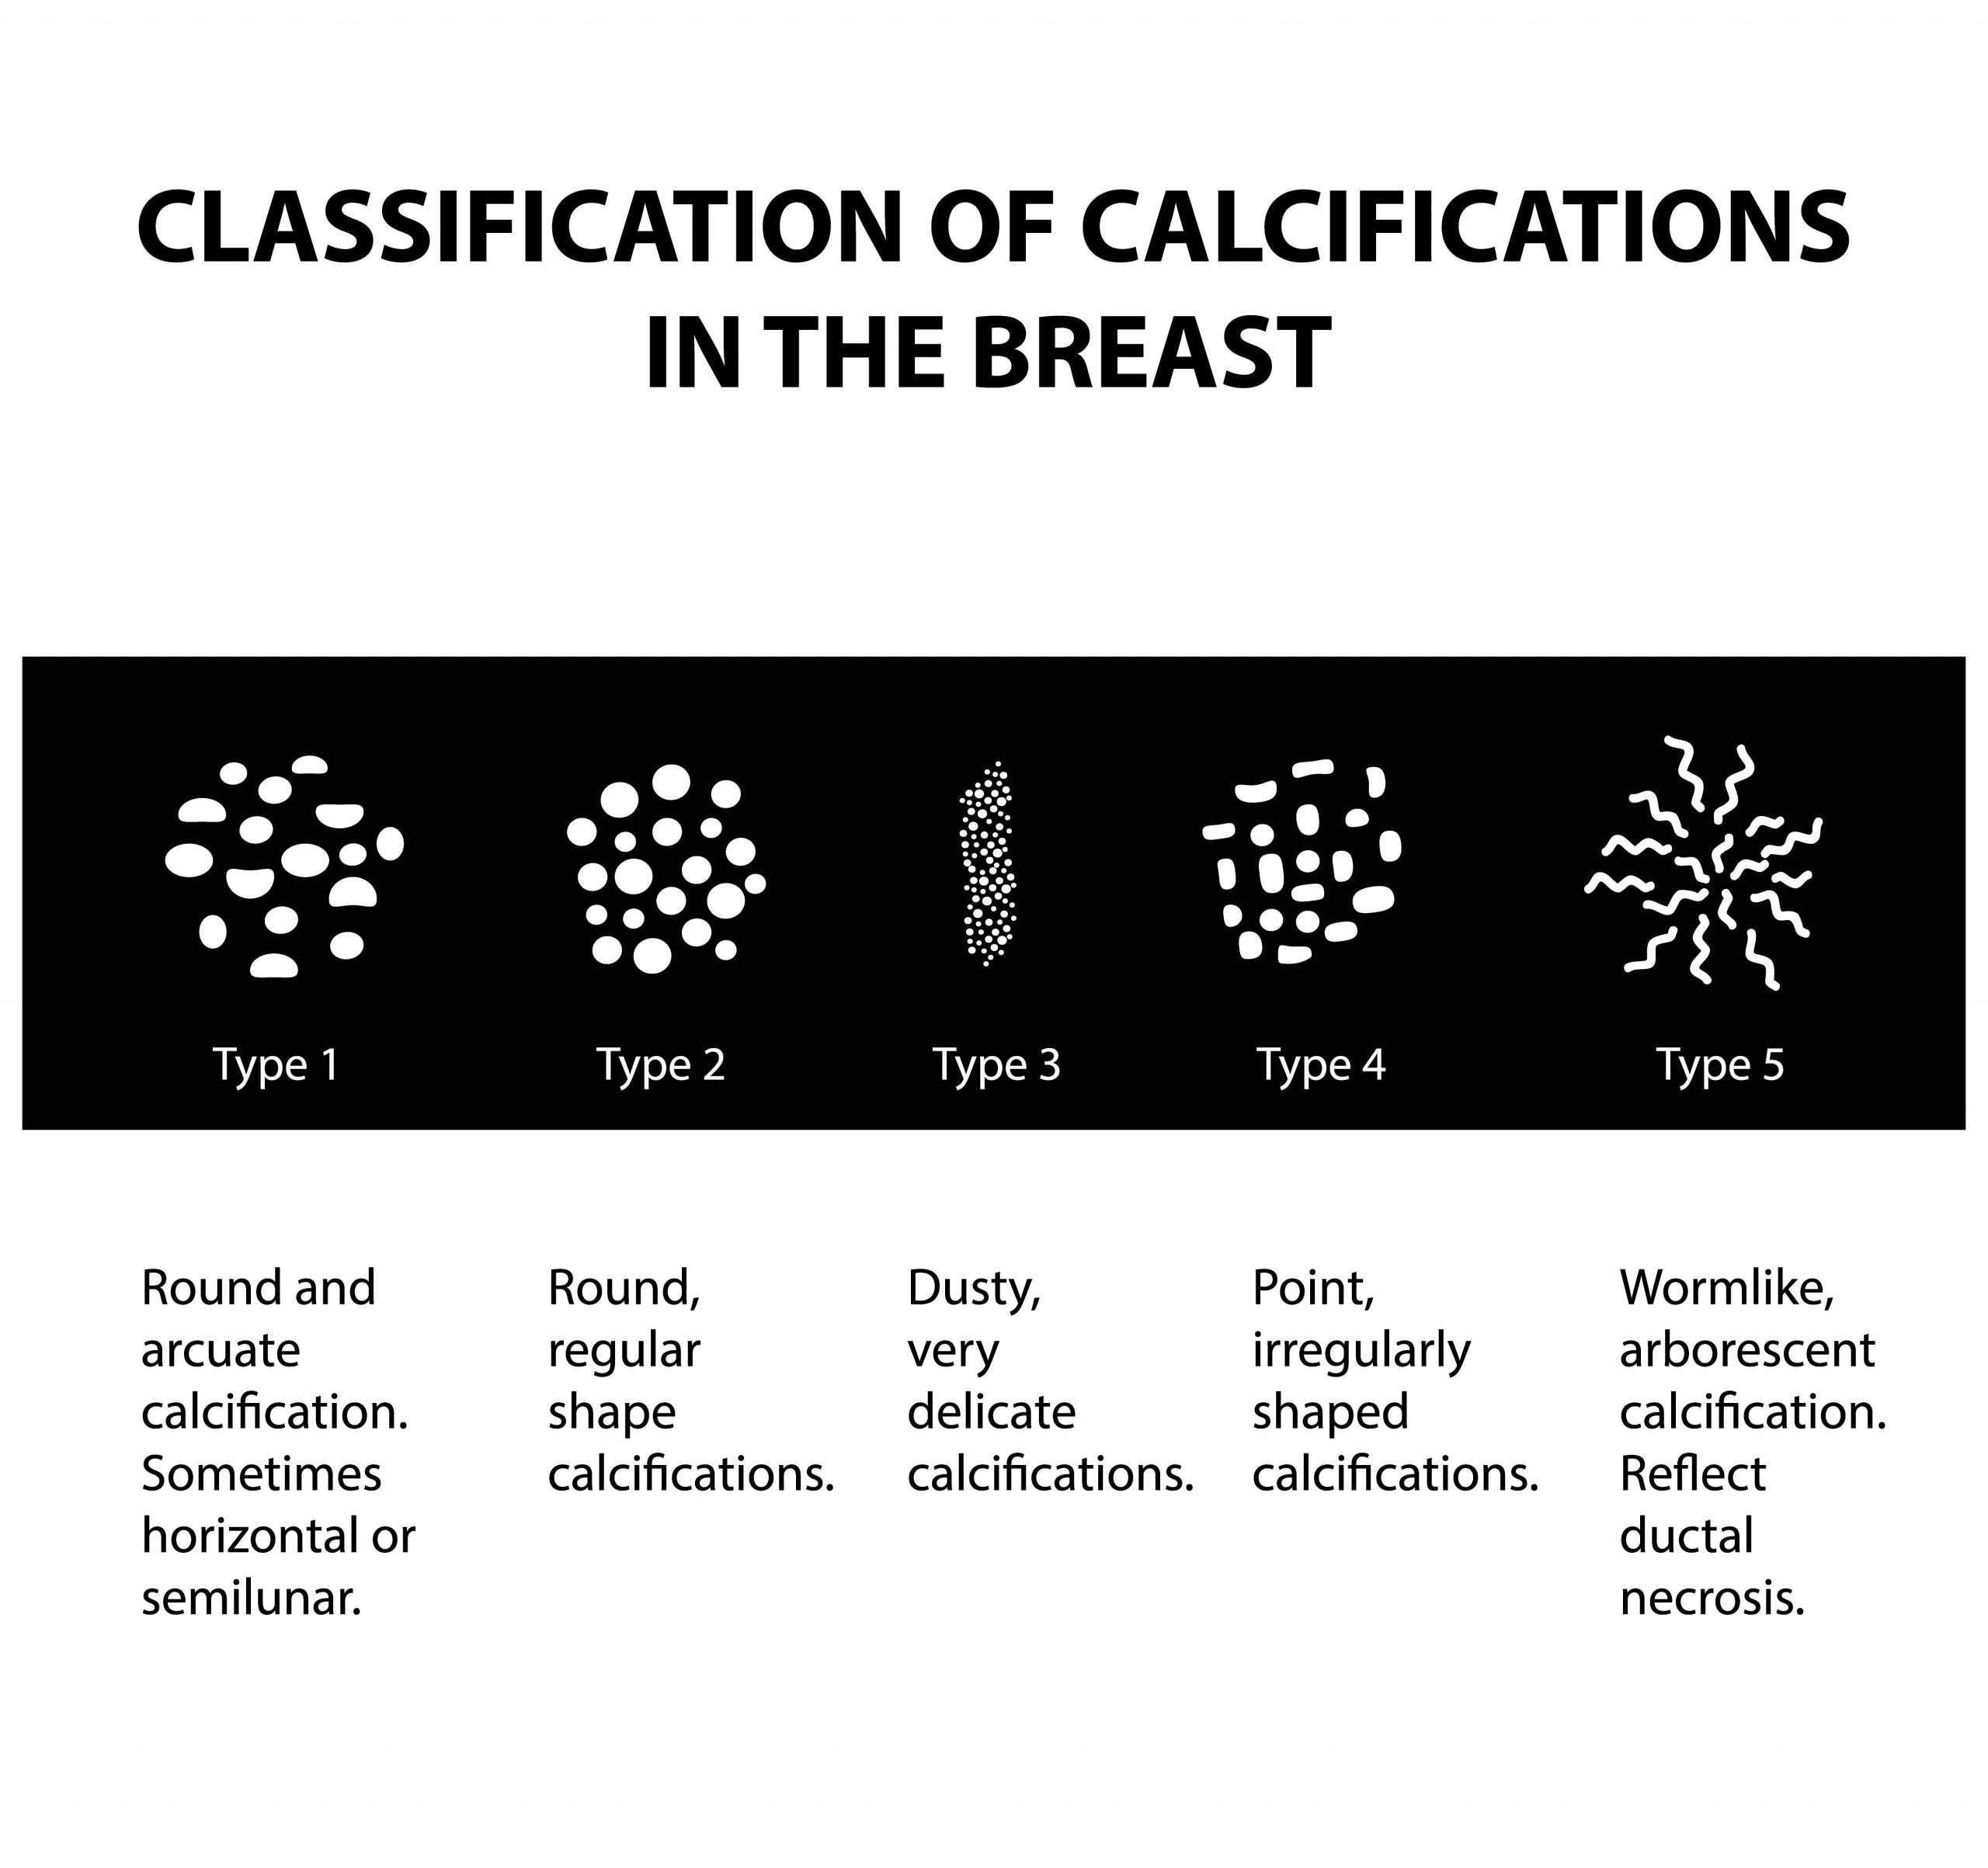

They appear as white spots or flecks on a mammogram but can't be felt during a breast exam. A new group has formed. For women treated for breast cancer in the past, calcifications may also be due.

There are numerous causes for calcium deposits in the breasts, including: But, japanese food natto has the ability to decalcify and maintain uniform level of calcium throughout the body and parts. Breast calcifications. california pacific medical center:

There are a significant number. This is especially good for. Calcifications in a noncancerous growth called a fibroadenoma.